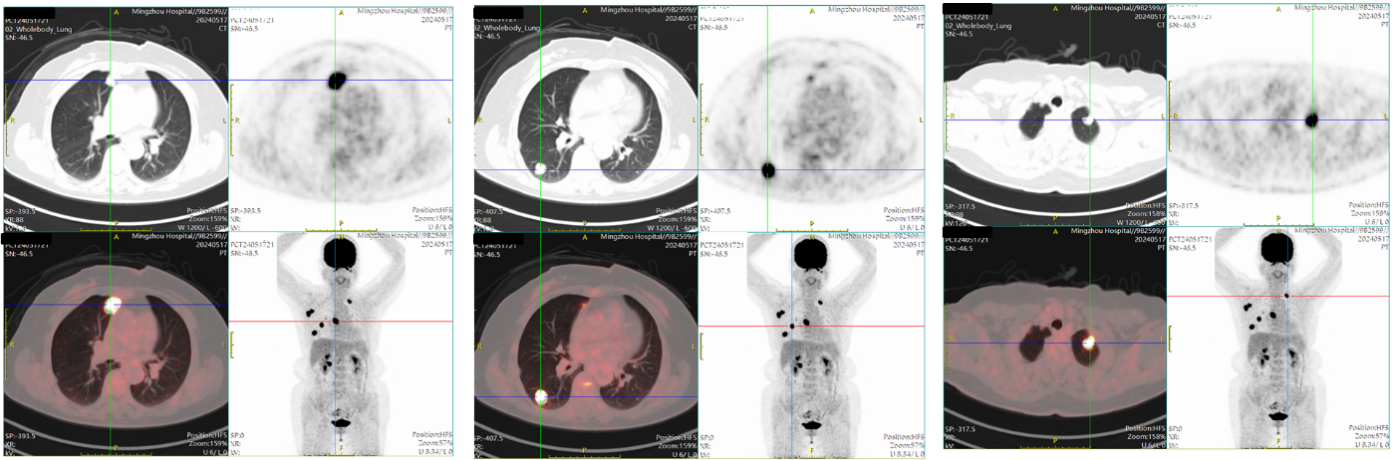

PET-CT(2024 年 5 月17日):右侧乳腺癌伴右腋窝多发淋巴结转移、双肺多发转移瘤。

图2 2024年5月17日PET-CT